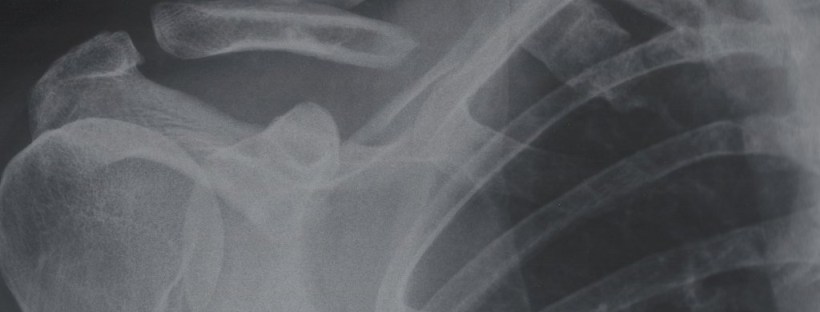

Crack !?! … le bruit classique retentit et vous savez que c’est une fracture. Après une visite chez le médecin, une radiographie, un plâtre ou une attelle et six longues semaines d’attente, vous êtes finalement libre de bouger. Cependant une mauvaise surprise vous attend, votre articulation est immobile, douloureuse et vous avez l’impression de ne plus avoir de force. La bonne nouvelle est que tout cela est réversible ! En physiothérapie nous voyons fréquemment ce genre de situation.

Tout d’abord, il faut comprendre pourquoi cette raideur, cette douleur et cette faiblesse se produisent suite à la fracture. En fait, tout cela est en grande partie une conséquence de l’immobilisation. Pour permettre à la fracture de bien guérir, on doit l’immobiliser de façon prolongée, mais ce traitement initial a un prix. Les autres tissus autour de l’articulation sont aussi immobilisés et s’ankylosent. Les muscles, eux s’atrophient car ils ne sont pas utilisés. La douleur quant à elle se poursuit même quand l’os est guéri, mais demeure près du trait de fracture.